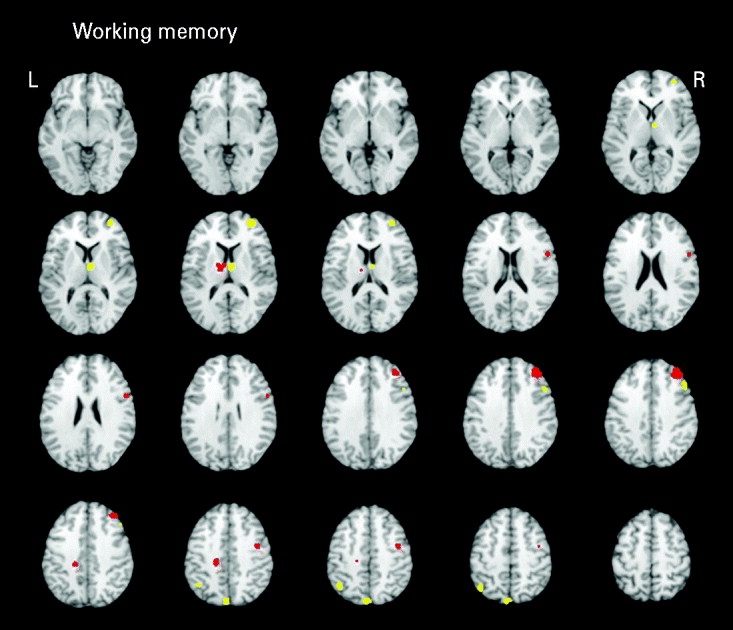

Working memory

Seven studies (eight samples) used tasks categorized as primarily measuring working memory. Studies in the domain of working memory demonstrated mostly consistent activations with the all-studies functional activation map (Table 3 and Fig. 3). One notable difference from the all-studies activation map included the finding that, although both hypo- and hyperactivity were found in relatives, they were not found in overlapping middle frontal regions. This analysis suggests that the working memory studies contributed greatly to the all-studies activation map; however, it was the combination of all studies that led to the finding of hypo- and hyperactivity in the overlapping middle frontal regions.

Fig. 3. Above-threshold brain activations for contrasts of controls greater than relatives (red) and relatives greater than controls (yellow) for working memory studies. L, left; R, right.